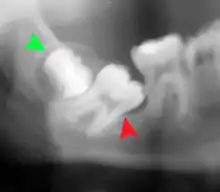

Impacted wisdom tooth with a backward tilt (distoangular impaction) and chronic infection to back of crown (green arrow)

Impacted wisdom tooth with no tilt (vertical impaction)

Impacted wisdom tooth that is tilted forward (mesioangular impaction)

Impacted wisdom tooth with a horizontal orientation (horizontal impaction)